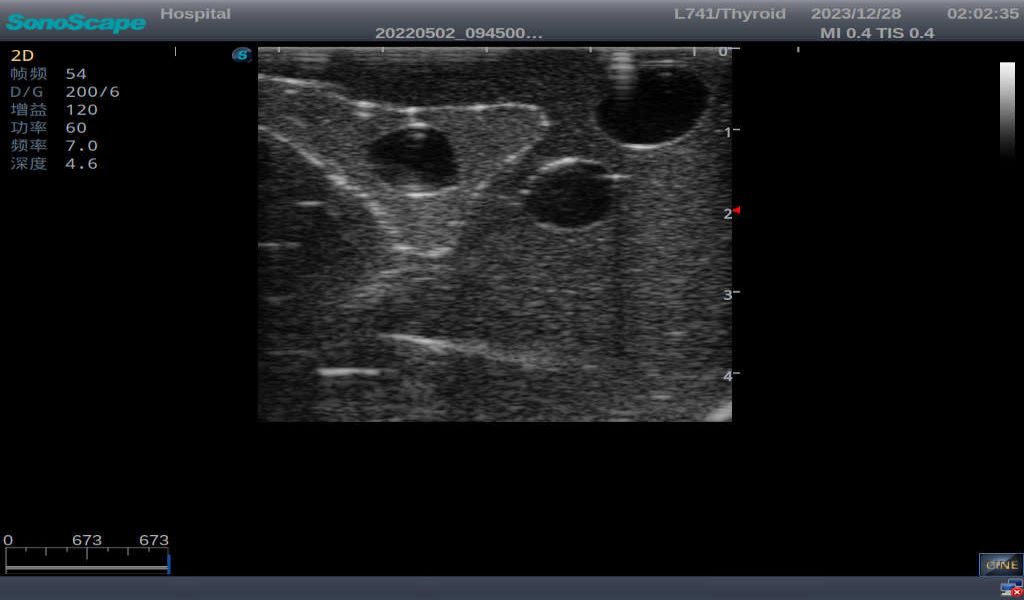

3) It comes with four (4) thyroid modules and can show five (5) ultrasonic images: normal thyroid, thyroid adenoma, thyroid cancer, nodular goiter, thyroid cyst

Normal thyroid with homogeneous parenchymal echo and well-defined capsule

Thyroid adenoma with well-defined border and smooth uniform halo

Thyroid cyst, which fluid area, dark and echo-free area can be seen